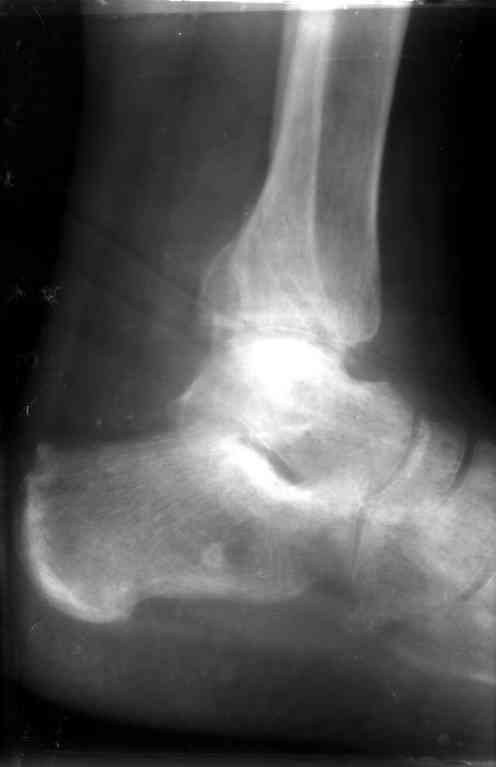

Перелом обеих лодыжек и з/края б/б кости с вывихом стопы,new |

Металлоконструкции удалены через 7 недель с момента травмы, после чего еще месяц иммобилизации, осторожная дозированная нагрузка. Спустя 3,5 месяцев имеем следующее.